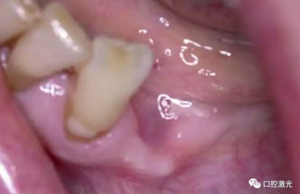

術(shù)后即刻,薄膜層的形成

術(shù)后3天